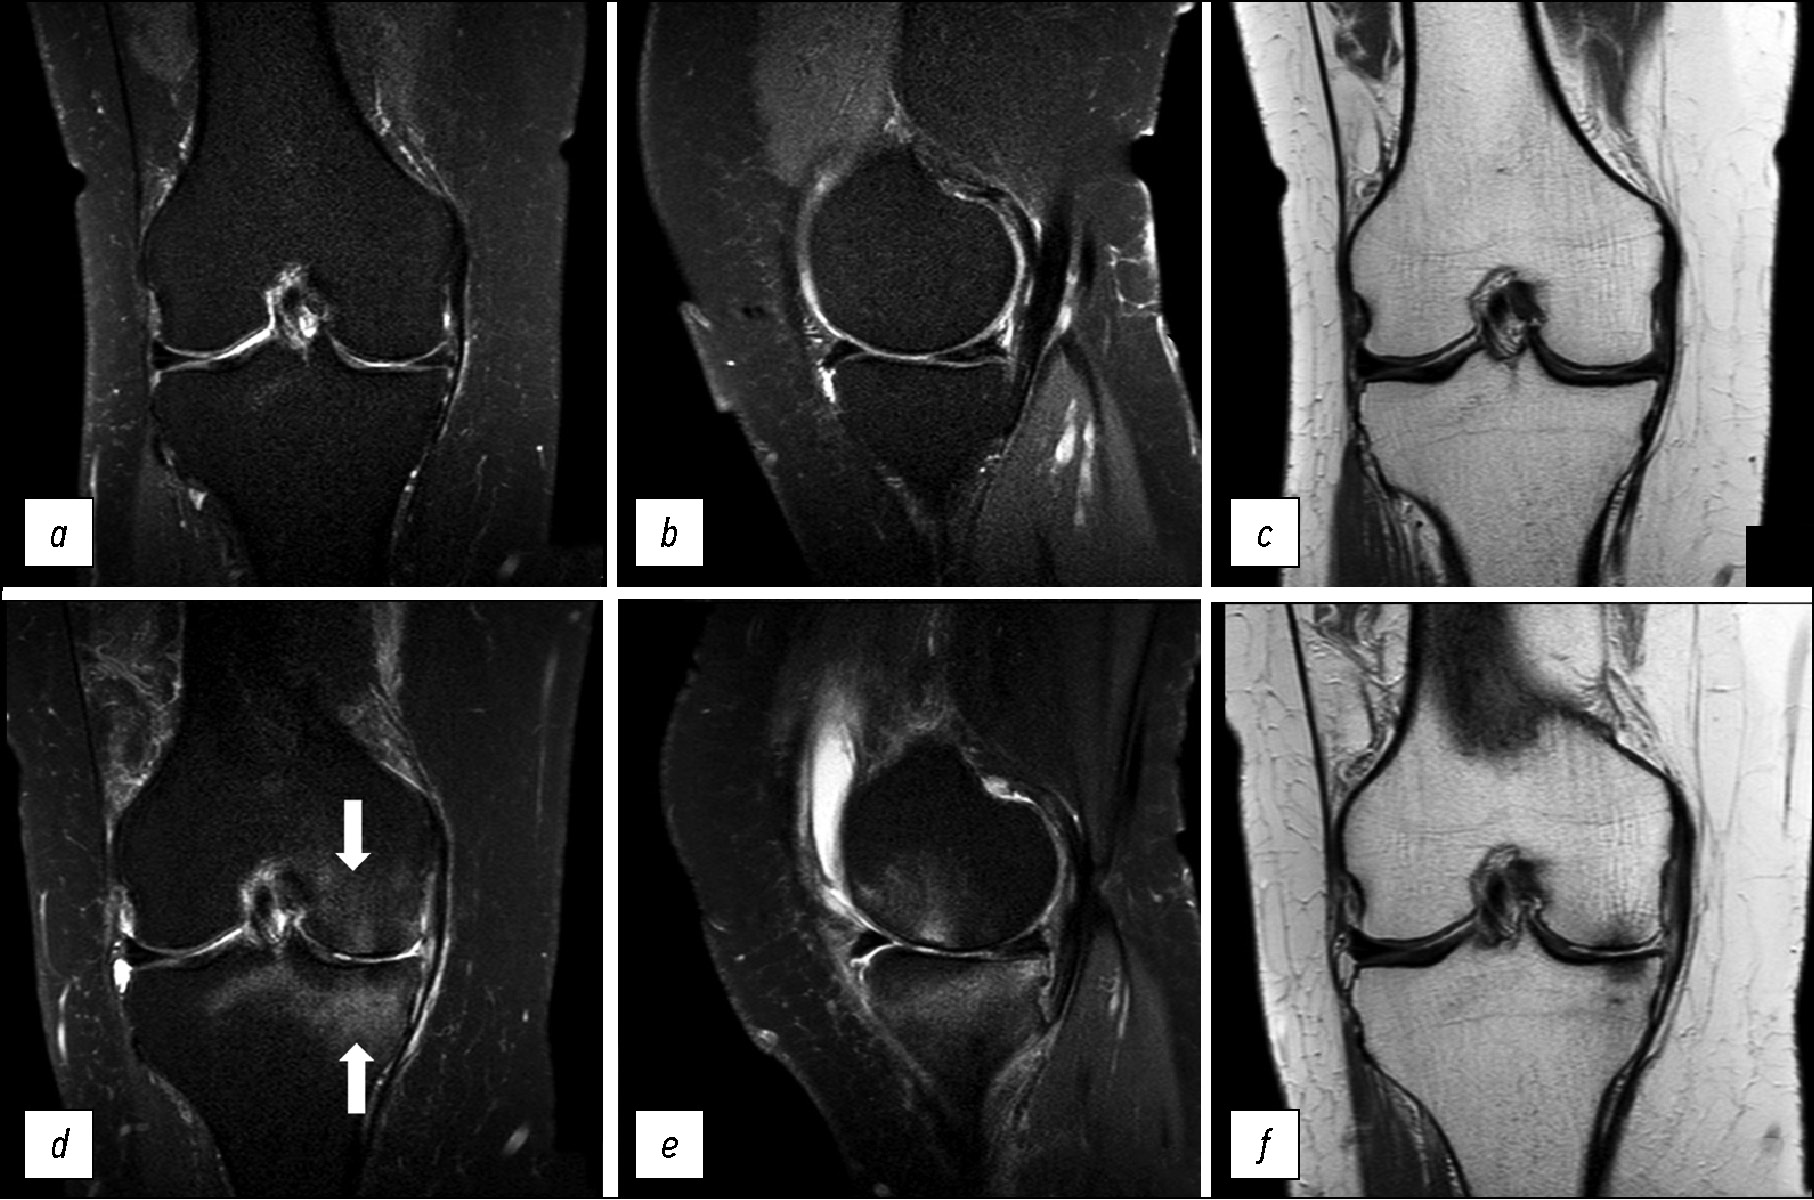

Пациентка К., 68 лет, обратилась с жалобами на резкую боль в области правого коленного сустава. Боль возникла без видимой причины. В анамнезе есть указание, что 6 месяцев назад больная наблюдалась с диагнозом «транзиторный отёк головки левой бедренной кости». На фоне консервативной терапии, со слов пациентки, процесс был купирован. После выполнения МРТ-исследования коленного сустава (рис. 4) выявлены изменения в области внутреннего мыщелка бедренной кости, которые стали основанием для диагноза «транзиторный отёк внутреннего мыщелка правой бедренной кости».

Рис. 4. МР-томограммы коленного сустава: а, b — корональная и сагиттальная проекции в режиме PD с подавлением сигнала от жировой ткани при транзиторном отёке внутреннего мыщелка правой бедренной кости, c, d — корональная и сагиттальная проекции в режиме PD с подавлением сигнала от жировой ткани через 3 месяца после начала лечения (полное восстановление костной ткани внутреннего мыщелка бедренной кости); е — графическое изображение.

Fig. 4. MRI scans of the knee: а, b — coronal and sagittal views in to suppress the signal from adipose tissue with a transient bone marrow edema (TBME) medial condyle of the femur, c, d — coronal and sagittal views in to suppress the signal from adipose tissue after 3 months after start of treatment — bone restoration. Graphic image of a transient bone marrow edema (TBME) (е).

Особенностью транзиторного отёка костной ткани является его равномерное распределение на большей площади мыщелка, без дополнительных включений и линий. Визуально не отличается от начальных стадий идиопатического асептического некроза, поэтому диагноз «транзиторный отёк» может быть установлен только после разрешения отёка и полного выздоровления пациента.